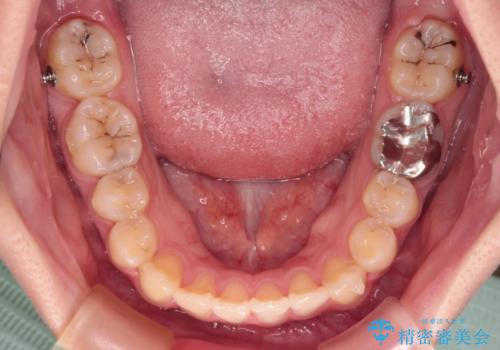

- 左右の八重歯を気にして来院された患者様です。

歯列としてはインビザラインでもワイヤー矯正でも対応できるものでしたが、インビザラインによる治療を希望されていました。

上顎の八重歯改善にインビザラインでは時間のかかってしまう可能性があり、更には口元が治療前よりも突出してしまう可能性があったため、補助装置により八重歯を事前に引き込んでおくことで、インビザラインによる治療をスムーズに行えるように計画しました。

補助装置を使用したことで、口元が突出することもなく、スムーズに仕上げることができました。